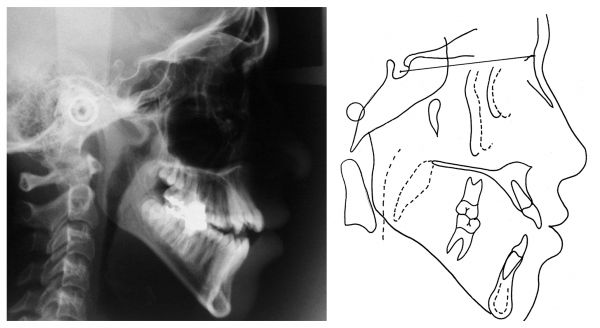

Radiografia inicial

Telerradiografia e traçado final

Superposições cefalométricas